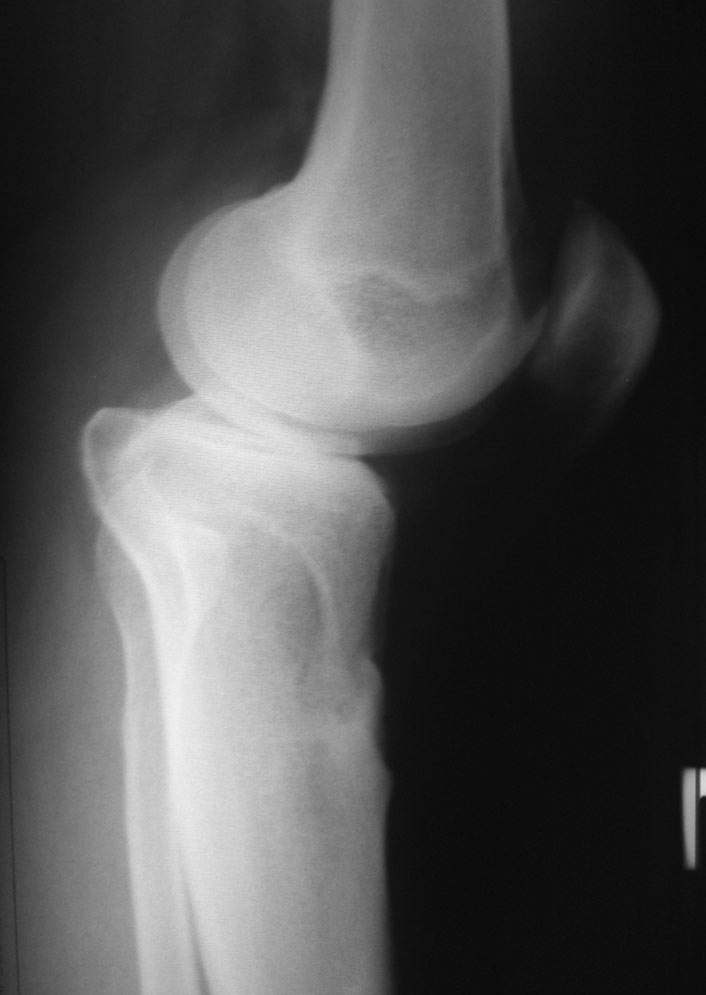

Уважаемый доктор Зайцев! Причина деформации проксимальной тибии у Вашего пациента - преждевременное и несимметричное закрытие зоны роста передней части проксимальной ростковой зоны б/б кости в следствии окультной травмы произошедшей в возрате 10-12 лет. Есть 2 причины рекурвационной деформации в области коленного сустава - мягкотканевая и костная.В данном случае Вы имеете дело не с рукурвацией коленного сустава, а с рекурвационной деформацией проксимальной голени. "Заднего выдвижного положения" на самом деле нет.То, что Вы видите на боковом снимке - это не задний подвывих голени - это снимок, сделанный в сгибании коленного сустава. Дело в том, что костные дефорсации в области коленного хорошо компенсируются за счёт движения в суставе. поэтому то, что вы видите, как задний подвывих на самом деле - сгибательное положение колена.

Это можно проверить очень просто - надо сделать стресс рентгенограмму в положении полного разгибания коленного сустава.Для этого посадите больного на стул, пятку поставьте на другой стул, дайте пациенту кассету 30Х40 держать с наружной стороны колена, и попросить ренгентехника сделать латеральный снимок с втутренней стороны. Сделав снимок здорового колена, Вы сможете расчитать деформацию.

10.-Рассмотрим представленную деформацию в боковой рентгенологической проекции.

Несложные расчеты на изготовленной скиаграмме (см. рис.1 ) показывают ,что суставная поверхность проксимального отдела б/б кости, находится в положении сгибания примерно 30 гр. Плоскость деформации лежит в сагитальной плоскости. Истинный угол деформации равен примерно 15 гр., с вершиной на 4-4.5 см. (примерно) дистальнее края суставной поверхности.

Вам представленна склаграмма боковой R – гр болного вынесенного на обсуждение.

А – ось бедра.

Б – линия Blumensaat/

В – имеющаяся линия суставной поверхности б/б кости.

Г – положение суставной поверхности в норме, по отношению к продольной оси б/б кости.

Д – продольная ось голени.

86 гр. (Г-Д) отношение суставной полверхности к оси голени.

~ 30 гр. – положение сгибания.

Рисунок 1-взаимоотношение в коленном суставе.